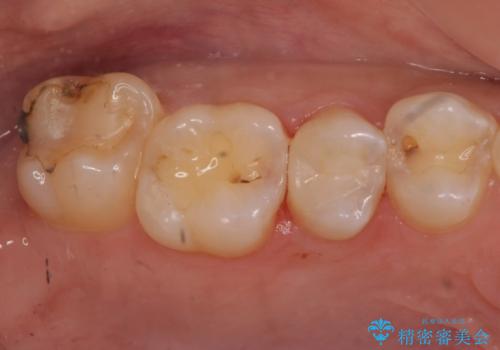

- 全体的にむし歯を治していきたいとのことで来院。

検査の結果、症状はないものの右上の奥歯に虫歯が見つかりました。

笑うと外からも見える位置であるため、白いセラミックでの治療となりました。

局所的に深い虫歯が確認されましたが、神経は温存することができました。

歯と歯の間から広がる虫歯は目視では確認しにくいため、定期的にチェックし悪化を予防することが大事です。